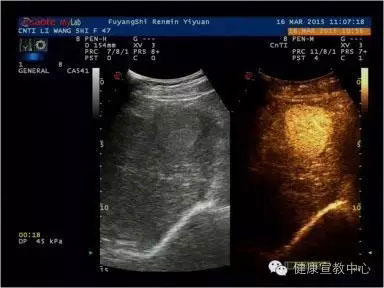

(甲乳分級診斷彈性評估技術(shù))

目前,科室開展的聲學(xué)造影已廣泛應(yīng)用到肝臟、膽囊、胰腺、腎臟、脾臟、子宮、甲狀腺、乳腺、淋巴結(jié)等,特別是在乳腺癌診斷尤其是早期病變甚至是癌前期病變的診斷中均取得突破性進(jìn)展。超聲造影、彈性成像及超聲甲、乳結(jié)節(jié)綜合分類法均為2014年在皖北率先相繼開展的新技術(shù),兩年多以來共開展造影500多例,200多名患者從中受益。隨著我院南區(qū)的全面開診,甲、乳診療中心及其他超聲學(xué)科聯(lián)合體的創(chuàng)立、高端機(jī)器設(shè)備的添置,聲學(xué)造影、彈性成像等新技術(shù)會拓展到其他學(xué)科,如生殖中心、婦科及外傷性病變等等。

(超聲造影輔助分類)

(肝臟超聲造影)